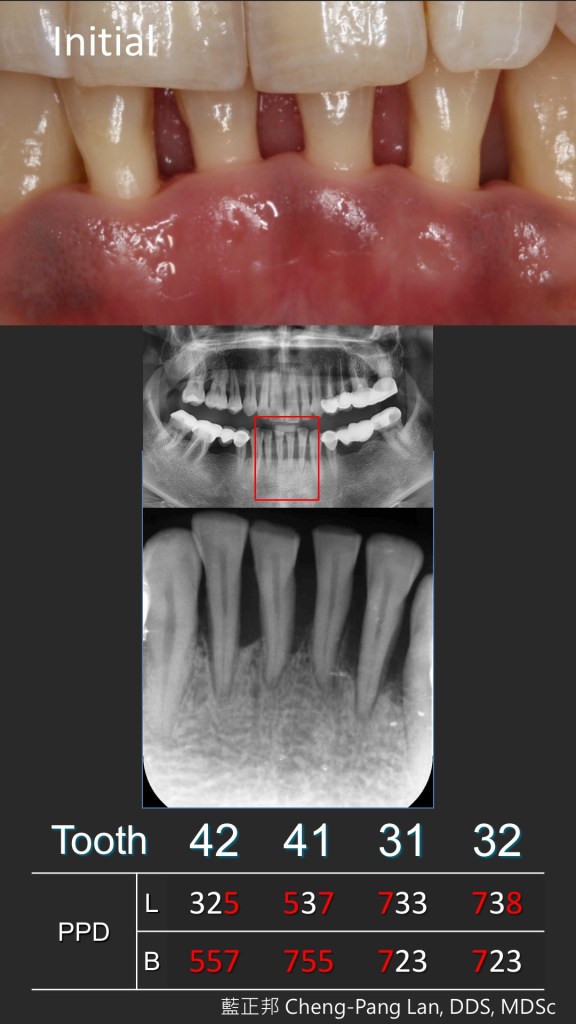

例如,36歲男性,不菸且身體健康。口腔衛生不錯,也無明顯結石與紅腫,但囊袋深及7~8mm,搖晃度頗高,隱約是一個困難案例。